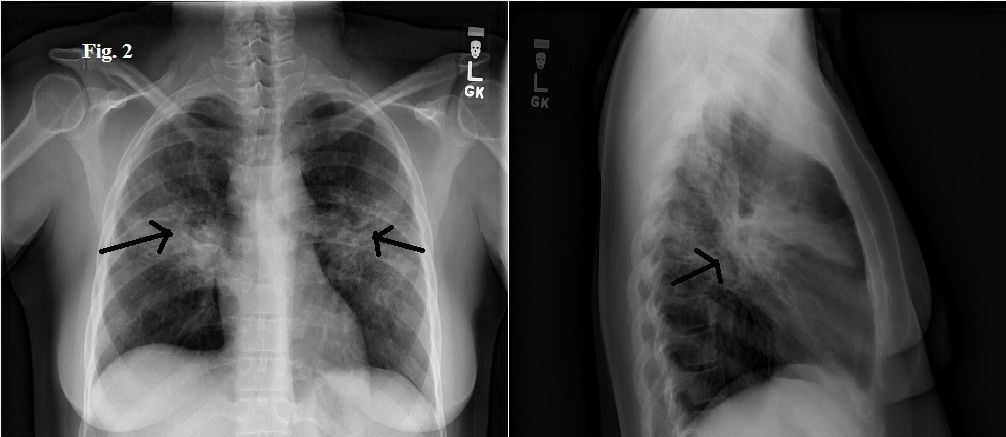

Figure 2. Repeated chest x-ray film.

A chest radiograph obtained 1 year earlier was notable for mild hilar prominence (Figure 1). (Click on images to enlarge.) A repeated chest radiograph showed new bilateral diffuse interstitial infiltrates involving both lungs, along with bilateral hilar lymphadenopathy (Figure 2). A chest CT scan showed similar findings with a tree-in-bud appearance predominantly in the midlung zones and perihilar areas (Figure 3). Tree-in-bud appearance describes a CT finding of centrilobular opacities which correspond to luminal impaction of bronchioles that become focally dilated with fluid, pus or mucus. Also seen was bilateral axillary, hilar, precarinal, and subcarinal lymphadenopathy. Pulmonary function testing (PFT) results showed a progression from moderate to severe obstructive lung disease and worsening diffusing capacity of the lung for carbon monoxide (DLCO).